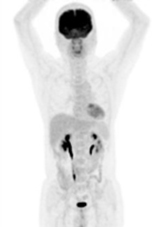

正常氟-18去氧葡萄糖於體內生理分佈

腫瘤細胞明顯增加代謝 (箭頭處)